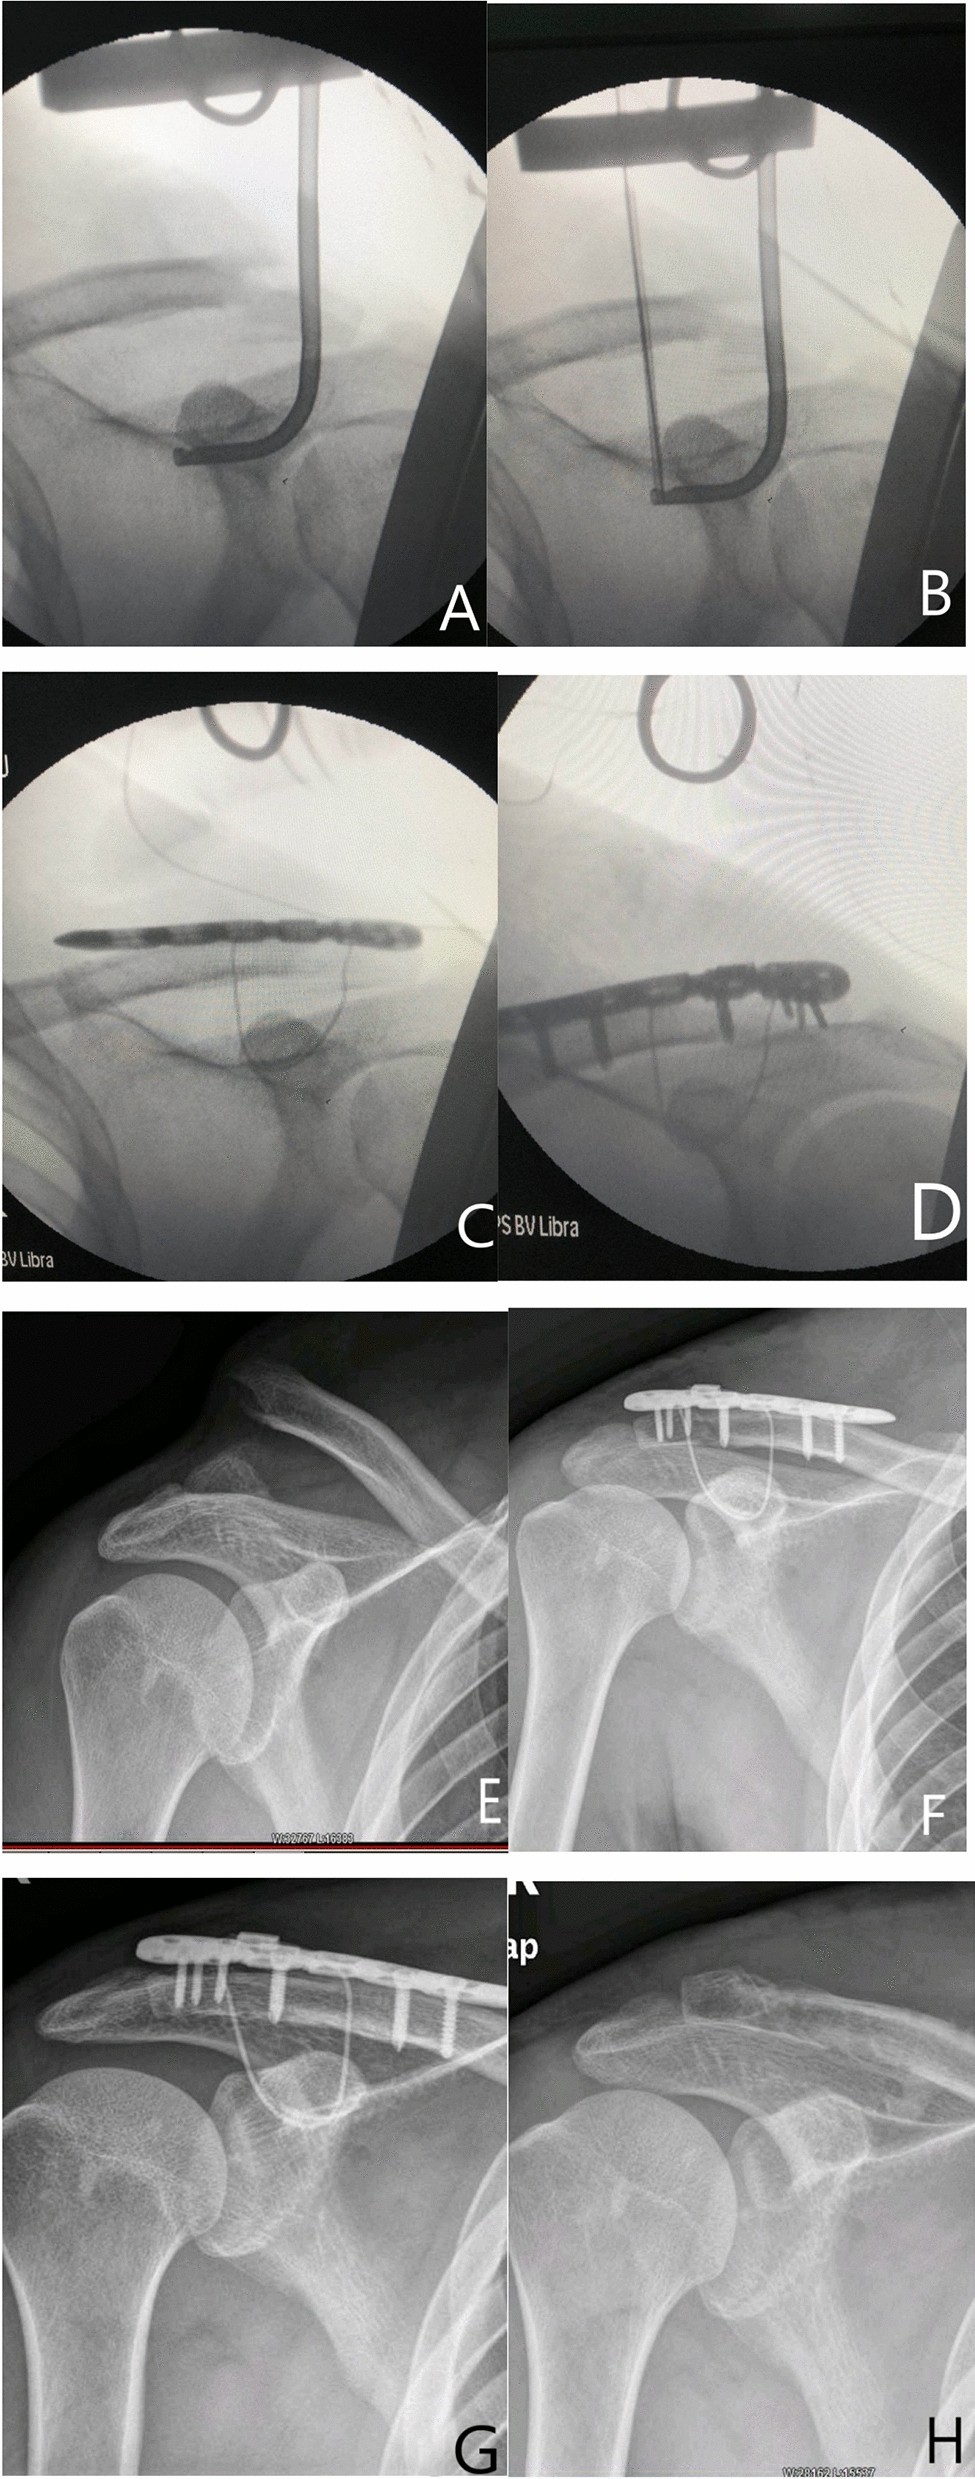

Treatment Of Distal Clavicle Fracture Of Neer Type Ii With Locking Plate In Combination With Titanium Cable Under The Guide Scientific Reports